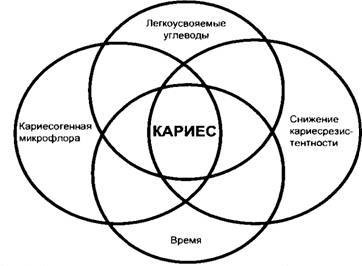

A megjelenése üregek által okozott négy összetevőből áll:

- Tooth (csökkentve a védő tulajdonságok)

- A mikroorganizmusok plakk

- szénhidrátok

- idő

Ennek hiányában egy ilyen alkatrészek nem fog fejlődni a fogszuvasodás.

Amint az ábrából látható, csak akkor, ha az összes kereszteződés körök (egybeesése mind a négy tényező) alakulhat szuvas folyamat.